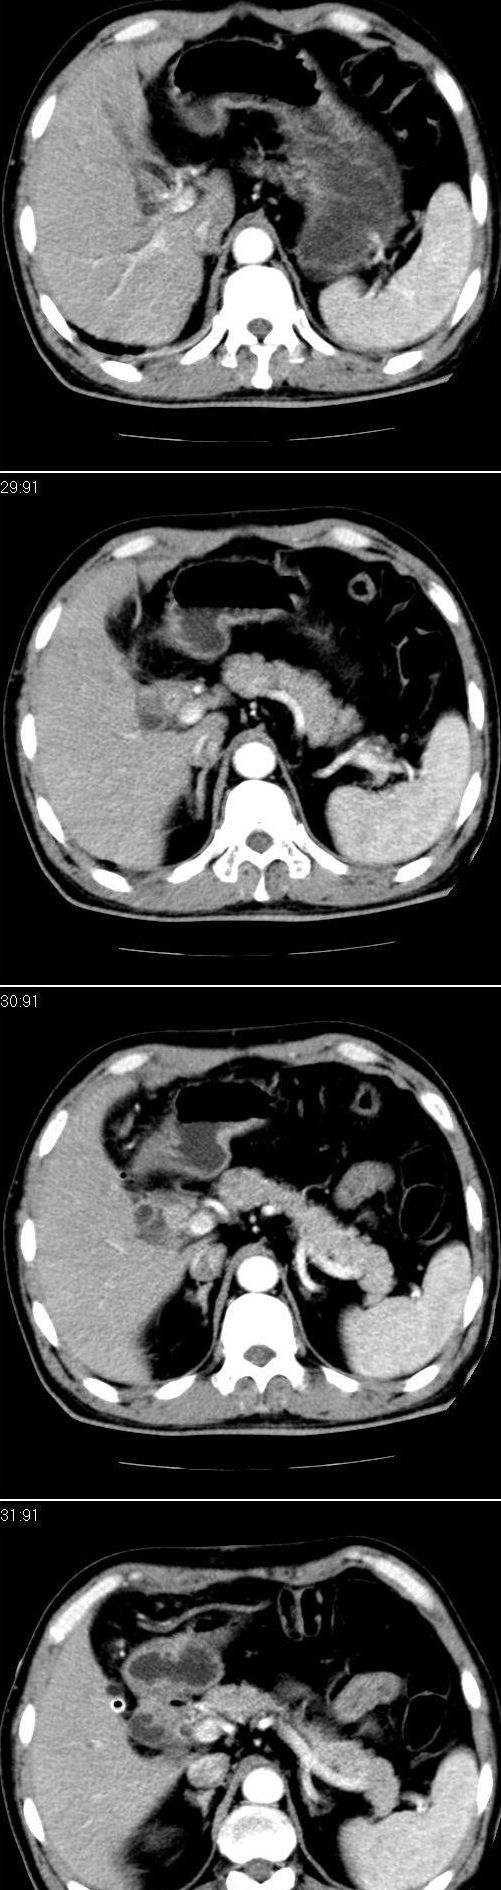

标题: CT13147:男,57岁。因胆结石阻塞性黄疸入院。 [打印本页]

标题: CT13147:男,57岁。因胆结石阻塞性黄疸入院。

男,57岁。因胆结石阻塞性黄疸入院。这是胆囊切除术后的照片,看看此片到底有什么问题。

肝内外胆管轻度扩张,胆囊窝内见引流管考虑胆囊切除术后改变.胃窦部软组织似增厚,建议胃镜检查.

在手术切除胆囊的过程中,发现肝门部胆总管恶性占位,因为家属不同意手术,没有切除,能看出来么?

肝内外胆管轻度扩张。楼主提示左右肝管合汇区域壁稍厚。胆总管末段壁似也稍厚有轻度强化。就现有资料诊断难。